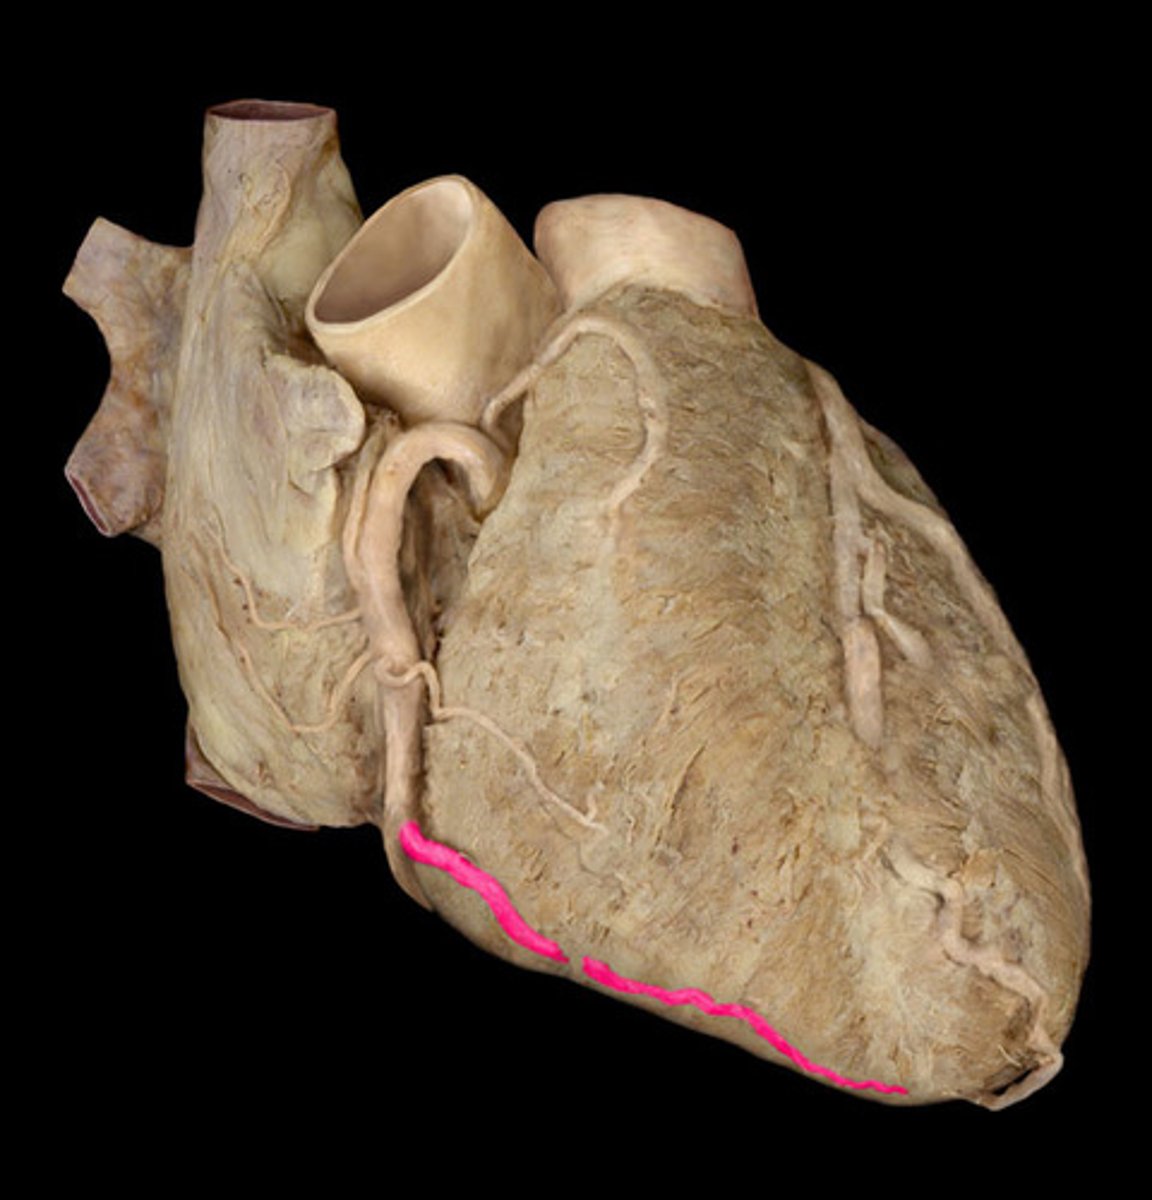

Inferior border of the heart

Boundary; X-ray, bottom edge

posterior interventricular artery

Structure; posterior side, crinkled ribbon in sulcus

H1

22